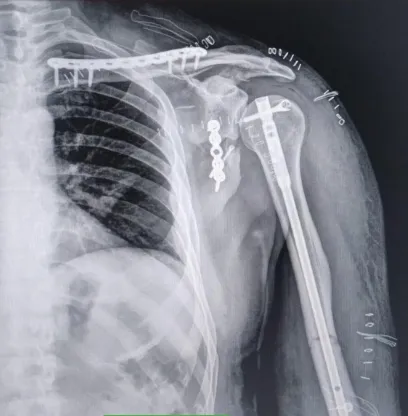

El paciente, Francisco Bazán, oriundo de Telén, sufrió un accidente mientras se dirigía hacia Rucanelo. Fue estabilizado inicialmente en Eduardo Castex y luego derivado a Santa Rosa, donde se le diagnosticó la compleja lesión.

El traumatólogo Darío Beascochea detalló que se aplicaron técnicas que hasta hace poco eran impensadas en la provincia, como la reparación de escápula mediante abordaje posterior minimamente invasivo, la fijación clavicular con placa deslizada y la colocación de un clavo endomedular en el húmero. Además, se realizó una neurólosis del nervio radial, lo que permitió recuperar buena parte de la movilidad del brazo en pocos días.

“La intervención fue inmediata, precisa y con mínima agresión a los tejidos. Al día siguiente, el paciente ya no presentaba dolor, lo que es sumamente destacable en estos cuadros”, explicó Beascochea.